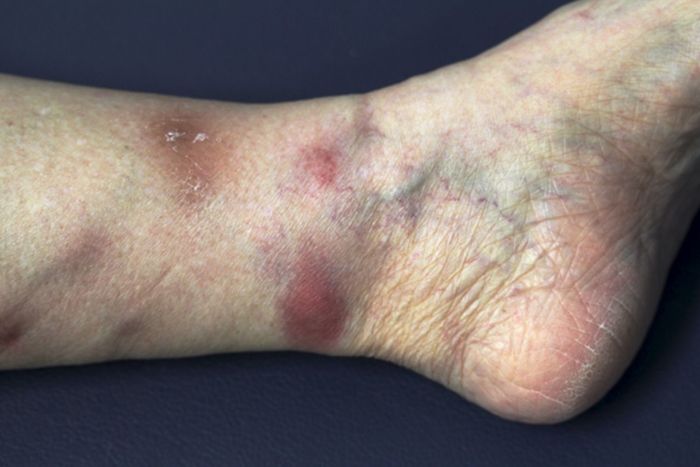

Image Description

An image of an EN lesion would typically show raised, erythematous nodules, varying in size from a few millimeters to several centimeters. The nodules would appear tender and slightly warm to the touch. The skin surrounding the nodules may be erythematous. The location of the lesions is typically on the shins, although other areas can be affected.

The skin might appear slightly indurated, with evidence of inflammation.